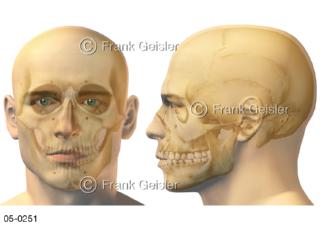

Bildergalerie Skelettsystem

Bilder zum Skelettsystem zeigen die Stützstruktur des menschlichen Körpers, die Knochen, eine besonders harte Form des Bindegewebes und Stützgewebes, welche das menschliche Skelett bildet, die Knochen des Stammes, der Extremitäten sowie der Gelenke